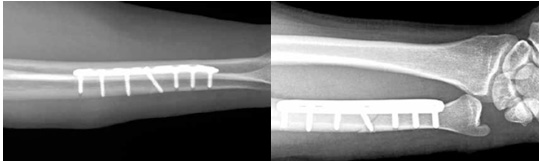

아래 사진은 고식적 방법의 척골 단축술이며 국내 또는 국외에서 많이 시행되고 있는 방법입니다. 4mm 이상의 뼈를 단축할 수 있고, 장점이 많으며 좋은 결과를 보고하고 있으나, 절개부위가 크며 절골술 부위의 불유합이 발생할 수 있다는 단점이 있습니다.

본원에서는 원위 골간단부 척골단축술과 관절내시경 치료를 주로 시행합니다. 절개부위를 최소화 하고 불유합 가능성을 낮추며, 한번의 절개로 삼각섬유연골 봉합까지 같이 시행할 수 있다는 장점이 있습니다.